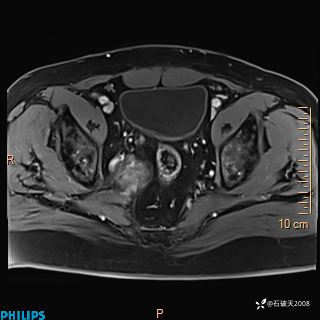

2023年3月份MRI影像

增强轴位